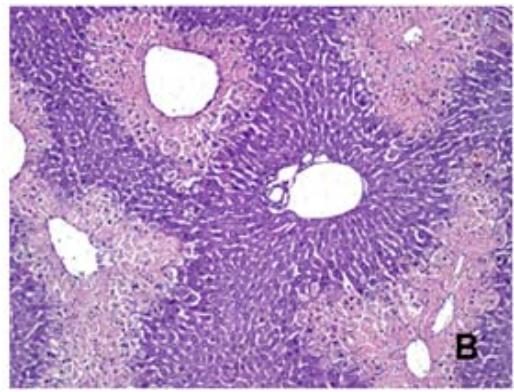

Na análise histológica, observou-se que o G2 (Tabela 1 e Figura 4B), que recebeu uma dose de APAP (500 mg/kg), apresentou necrose centrolobular multifocal, com predominância no escore 3 (3/6, $50\%$ ) ou seja, apresentando um nível de necrose de até $50\%$ do fígado. O G3 (Tabela 1 e Figura 4C) que recebeu pré-tratamento com silimarina (100mg/ Kg), demonstrou predominância nos escores 3 (2/6, $33,3\% )$ e 4 (2/6, $33,3\% )$, apresentando um nível de necrose hepático de

$50\%$ na maioria dos animais. O G4 (Tabela 1 e Figura 4D), que recebeu a dose de APAP $( 500 \mathrm { \ m g / k g ) }$ e pré- tratamento com EBUM (100 mg/Kg), exibiu predominância do escore 3 (4/6, 66,6%), mostrando um nível de necrose de até $50\%$ do fígado. O G5, que recebeu a dose de APAP (500mg/kg) e pré-tratamento com EBUM (500 mg/Kg), houve predominância do escore 2 (4/6, 66,6%), (Tabela 1 e Figura 4E), com um nível de necrose hepática igual ou inferior a $25\%$.

Escore 0 (sem necrose); escore 1 (necrose $< 10\%$ do fígado); escore 2 (necrose entre $10 \mathrm { - } 25\%$ do fígado); escore 3 (necrose entre $25 \mathrm { - } 50\%$ do fígado); escore 4 (necrose $> 50\%$ do fígado). Esses resultados podem ser visualizados na Figura 4, que inclui fotomicrografias representativas e a porcentagem de área de necrose hepática.

FAnálisehistopatológicao tecido hepáticocamundogos Swiss intoxicados codosúicaacetaminof iotatagtiai çõot ivtoopticaqãt quantoFieesentauotivamenteagns fora corada hematoxilina e eosina (HE) e capturadas com um aumento de $100 \times$.